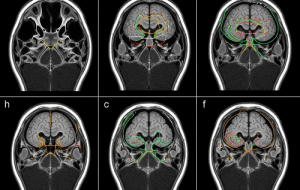

یه نظریه ۵۰ ساله در مورد «صداها»ی اسکیزوفرنی با یه مطالعه جدید تأیید شد

شواهد جدید یه نظریه قدیمی رو تأیید میکنه که میگه آدمای مبتلا به اسکیزوفرنی به این دلیل «صداهایی» رو تو سرشون میشنون که گفتار درونی خودشون رو به اشتباه به عنوان یه صدای خارجی تلقی میکنن. توماس ویتفورد، یه محقق روانشناسی از دانشگاه نیو ساوت ولز، میگه: «این ایده ۵۰ ساله که وجود داره، ولی